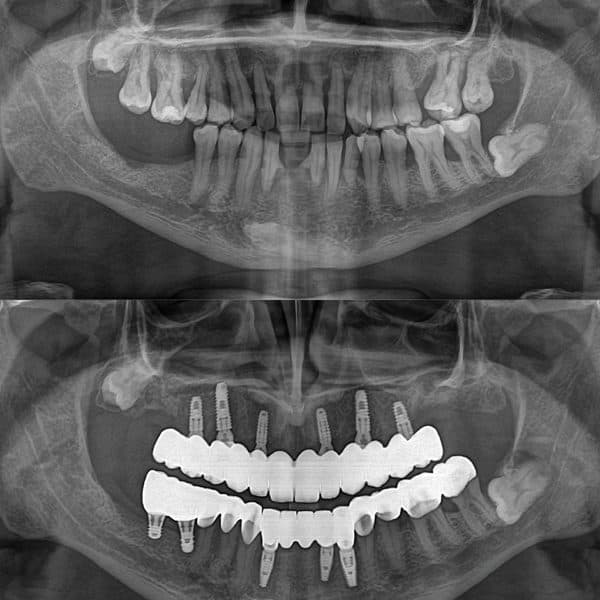

İmplant tedavisi öncesinde, diş hekimi, hastanın diş sağlığını değerlendirir. Çene kemiğinin durumu, dişeti sağlığı ve genel ağız yapısı incelenir. Bu aşamada, röntgen, 3D tomografi gibi teknolojilerle çene kemiğinin yapısı detaylı bir şekilde incelenebilir. Eğer çene kemiği yeterli değilse, ek tedavilerle kemik desteği sağlanabilir.

Lokal anestezi altında yapılan bu işlemde, diş hekimi, titanyumdan yapılmış implantı çene kemiğine yerleştirir. İmplant, çene kemiğine kaynaşarak doğal diş kökünün fonksiyonunu üstlenir. Bu aşama genellikle 1-2 saat sürer ve ağrı minimal düzeydedir. Teknolojinin ilerlemesiyle birlikte, implant yerleştirilmesi çok daha hızlı ve rahat bir işlem haline gelmiştir.

İmplant kaynaştıktan sonra, üzerine diş kronu veya köprü yerleştirilir. Bu kron, hastanın doğal dişlerine uygun olarak yapılır ve dişin estetik ve fonksiyonel açıdan uyumlu olmasını sağlar. Bu işlem sonrasında, hasta yeni dişini kullanmaya başlayabilir.